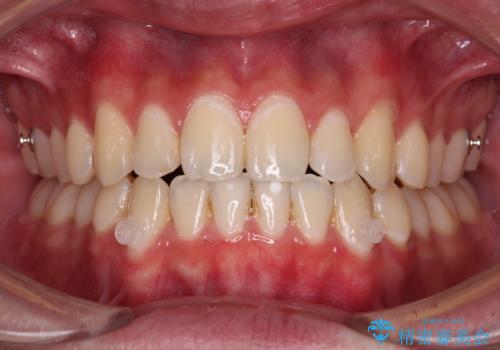

受け口傾向の咬み合わせ インビザラインできれいな口元に

受け口傾向の骨格であり、前歯はクロスバイトまたは切端咬合となっており、叢生は警備であったため、下顎を中心に歯列全体の後方移動を行い、IPR(歯と歯の間を削る)によってデコボコが解消するように設計し、インビザラインにより治療を行うこととしました。

受け口傾向のインビザライン矯正は比較的治療を行いやすいため、きれいに仕上げることができました。舌の突出癖が顕著であったため、改善のためのトレーニングをしっかりと行っていただきました。